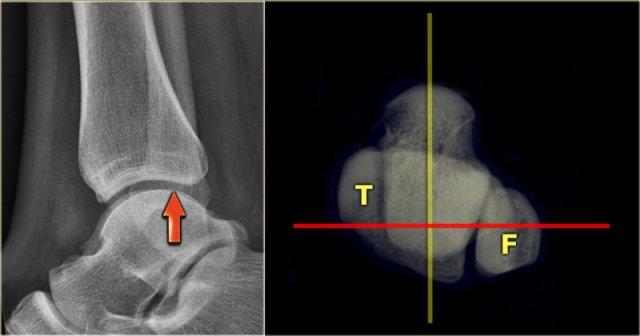

Lateral view

Nhiều người cho rằng để có hình ảnh bên tốt, xương mác xa phải nằm ở trung tâm của xương chày xa.

Tuy nhiên, do xương mác nằm ở phía sau nhiều hơn, xương mác phải chiếu lên phần sau của xương chày xa (mũi tên).

Malpositioning of the Lateral view

Định vị sai tư thế chụp nghiêng là lỗi phổ biến nhất trong chụp X-quang mắt cá chân bị chấn thương.

Vì bệnh nhân đang đau, kỹ thuật viên ngại để bệnh nhân xoay mắt cá chân hoàn toàn sang tư thế nghiêng.

Đây là một trong những lý do tại sao chúng ta bỏ sót rất nhiều gãy xương mắt cá sau.